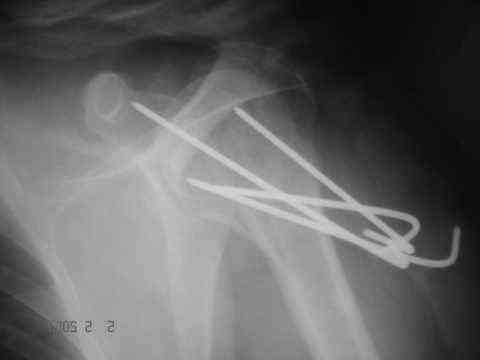

Dear all, A heavy built 30-year-old male patient sustained fracture dislocation of left shoulder about 8 months back.

For this ORIF with K-wires was done elsewhere. K-wires were removed at 6 weeks and patient advised physiotherapy. He has been doing physio dedicatedly since then.

It looks like the initial injury was a head splitting fracture. Presently the patient has a non-union at the level of the anatomical neck with displaced tuberosities. I would tackle the non-union, and would try to replace the tuberosities, a difficult procedure. I would use the proximal humerus locking plate from the AO.